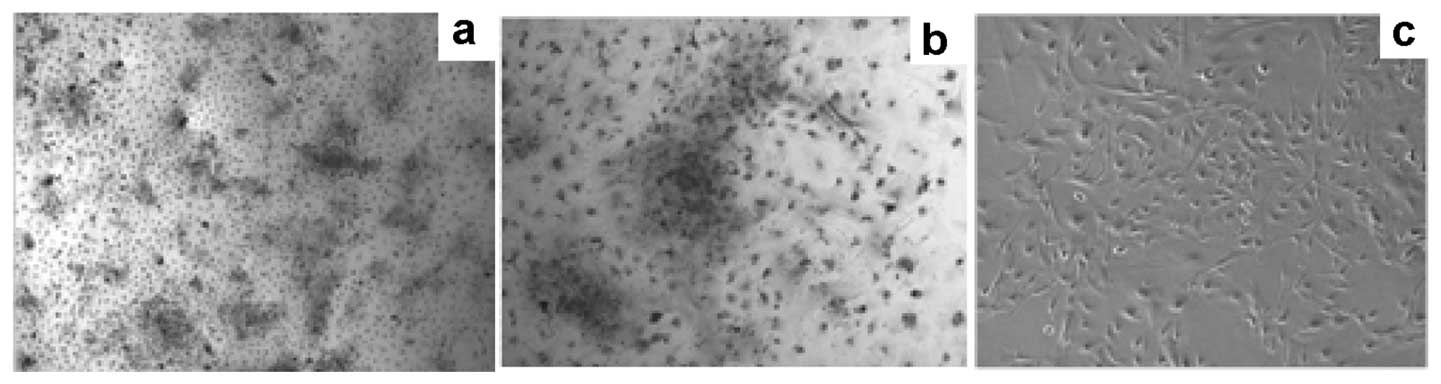

Prostate cancer (PCa) is the most common type of cancer worldwide. Mesenchymal stem cells (MSCs) can also be utilized as ‘tumor stromal cells’, which are associated with invasive and metastatic malignant tumor cells. Our study aimed to investigate MSCs in prostate tumors and normal MSCs and evaluate their differential characteristics. Normal MSCs (BMMSCs) were isolated from the femur and tibia of normal mice; prostate tumor MSCs (PCa-MSCs) were obtained from prostate tumors implanted in mice. These two types of MSCs were induced to differentiate into adipocytes, bone cells and chondrocytes. Growth curves were used to analyze the growth ability of PCa-MSCs and BMMSCs. Tritium-labeled thymidine (3H-TdR) was used to evaluate cell proliferation of RM-1 stimulated by MSCs. The time taken for PCa-MSCs to reach 90% confluence was markedly shorter than that of BMMSCs (8-10 vs. 12-14 days). The differentiation ability of PCa-MSCs was similar to that described in previous reports. The growth ability of PCa-MSCs was significantly higher than that of BMMSCs. The proliferative activity of PCa-MSCs was also higher than that of BMMSCs. Our data showed that PCa-MSCs exhibit identical characteristics when compared with those of MSCs. Additionally, their proliferative activity and growth ability were significantly higher when compared with these values in BMMSCs, which appear to have an intrinsic, cell-specific capacity to localize to PCa. The possible role of PCa-MSCs in the process of PCa development requires further clarification.

Figure 4